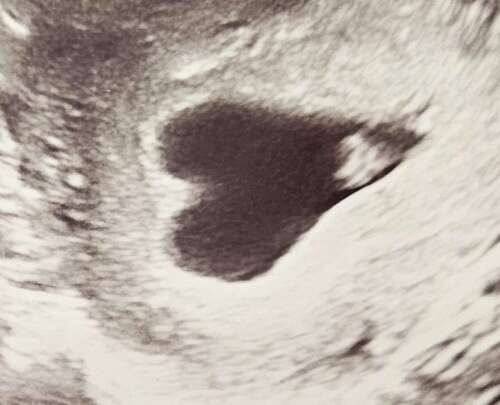

Ik kom net terug van mijn eerste echo. Ik ben 6+1 en het hartje klopt gelukkig! Maar ook een duidelijke hartvormige baarmoeder. De verloskundige maakte zich er niet direct zorgen om. Ze noemde alleen dat het dus meer kans geeft op een stuit. Ik merk dat ik nog even moet laten bezinken wat dit betekent..

Miskraam voor mijn tweede maar dat kan altijd gebeuren) Mijn schot loopt overigens bijna helemaal door soort van twee helften. Jij hebt wel echt een hartje ❤️. Succes en hopelijk gaat het allemaal goed.

Ik weet dat het een aandoening is, maar wat een prachtige foto…. Toch heel bijzonder

Wat een prachtige foto 💗